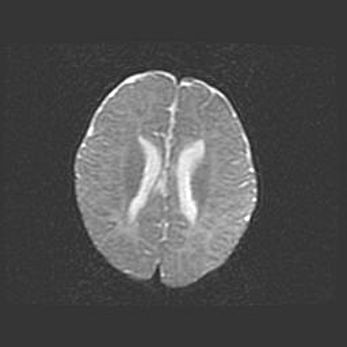

Множественные кисты обоих полушарий головного мозга, наибольшая из них в правой затылочной области. Ассиметричная атрофическая гидроцефалия.

Возраст: 7 месяцев

Вес: 5660 г

Пол: мужской

Окружность головы: 41,5 см

Срок гестации: 28-29 недель

Кисты головного мозга развиваются в результате многоочаговых некрозов вещества мозга и возникают вследствие перенесенной перинатальной инфекции, менингитов, энцефалитов, асфиксии, родовой травмы, расстройств мозгового кровообращения различного генеза. Образованию кист в веществе головного мозга плодов и новорожденных способствуют такие факторы, как высокое содержание в нем воды, недостаточная (или отсутствие) миелинизация и слабая астроглиальная реакция на повреждение.

Кисты могут сочетаться с гидроцефалией и другими поражениями головного мозга.